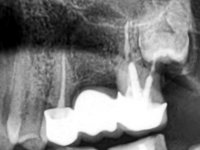

Male patient, 34 years old, non-smoker. Teeth 17 and 16 had extensive restorations with composite resin and placed intra-radicular posts. In the imaging examination, it was found that the endodontic treatment was not technically satisfactory, but had been asymptomatic for several years. The patient was rehabilitated with a 2-element bridge at 17 and 16 and 4 years later an abscess appeared in the apical area of 2.6. It had the 2.8 tooth included with a close relationship with the 2.7 root. During these 4 years there was no positional change of this tooth. After endodontic retreatment of teeth 27 and 26, an abscess appears again in the area of tooth 26, possibly associated with a root fracture. Given the history referred to in relation to tooth 26, it was considered a tooth with indicated extraction.

In a first phase, a 2-element bridge in Zr was proposed. in teeth 17 and 16. When 4 years later, an abscess appeared in tooth 26, the patient was proposed to remove the bridge, remove the intra-radicular posts and perform a retreatment of the endodontic treatments and put the bridge back. It was possible to do what we set out to do, but 1 year after this procedure, with the appearance of a new abscess, the extraction of tooth 26 was proposed. With this extraction, the patient was proposed to make a bridge in Zr. of 3 elements, with teeth 27 and 25 as abutments and 26 as a pontic.

Teeth 17 and 16 were prepared for the fabrication of a 2-element Zr bridge. The impression was performed with a double mixing technique and a monolithic bridge in Zr was made in the laboratory. 4 years later, an abscess appeared in the apical area of tooth 26. It was decided to remove the bridge, remove the intra-radicular posts and retract the endodontic treatments of teeth 17 and 16. The removal of the bridge was carried out by making two cervical cavities. in the palatal area of the bridge and with a microluxator, disinsertion movements were performed. The intra-radicular posts were removed using fine drills and an ultrasound tip. The bridge was provisionally cemented and the patient was referred to a fellow endodontist for endodontic retreatment. After the retreatment, the intraradicular posts were placed again and the bridge was definitively cemented. One year later, a new abscess appears, possibly related to a root fracture. The bridge was sectioned between tooth 27 and 26 and tooth 26 was extracted and the crown of 27 was provisionally cemented. 3 months later, teeth 27 and 25 were prepared and a temporary bridge was made in dual polymerization resin. Then, an impression was made using the double mixing technique and a 3-element bridge in Zr was made in the laboratory. It was permanently cemented in the mouth with resin-reinforced glass ionomer cement.